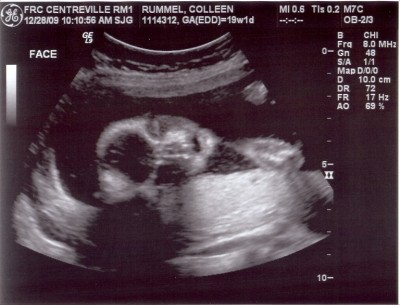

*pay no attention to the negligent mother hiding behind the computer screen*

I really and truly have been meaning to post these. But I really and truly did have an issue with my scanner. I would attempt to scan the images and it would say “uh, I’m sorry, which computer would you like these sent to?” and I’d remind it nicely that it would be for my cute little laptop. Then the scanner was all “whatever,” and wouldn’t send the images to my laptop. So I tried to dupe it by triggering the scanner remotely from my laptop (instead of the scanner itself), and I’ll be darned if the thing didn’t holler out at me “B**** please! I can see you in there!” and wouldn’t send me the images. So I was forced to ask Justin a few times to scan the sonogram images for me. I think I literally heard the scanner purr “oh, the Apple wants some images scanned? Sure! Whatever you want, sweetie!”

So cute. And if you have to ask what he’s doing back there, you probably don’t want to know.

So adorable! I can’t wait to see what this baby boy looks like on the outside!

So cute! I love sonogram pics.